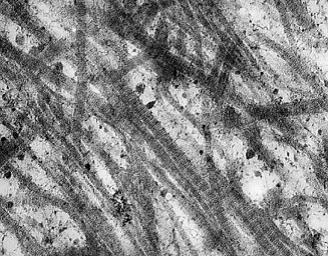

Fig 1 – Fibras de colágeno tipo I Fig 2 – Composição da cartilagem A qualidade geral da pele, a capacidade de retenção de umidade e a resistência são determinados pela camada estrutural mais profunda, a derme, onde os elementos de retenção de colágeno são encontrados. CARTIDYSS® age onde os cremes não alcançam – ajuda a apoiar e proteger os blocos vitais de construção da pele para os benefícios a longo prazo. Indicação • Estimula síntese de colágeno • Previne os efeitos do processo de envelhecimento • Aumenta a firmeza e elasticidade da pele • Reduz as rugas • Promove o auto-preenchimento da pele • Fortalece cabelos e unhas • Promove hidratação profunda das rugas